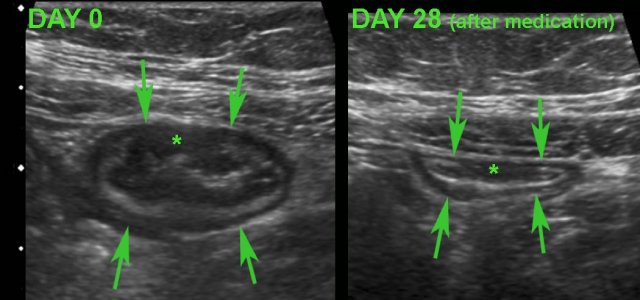

Monitoring disease activity during medication

US can also be used for monitoring disease activity during medical therapy for Crohn’s disease, particularly in circumscribed Crohn's disease of the terminal ileum or colon and in well-circumscribed and reproducible  lesions.

Monitoring disease activity in response to medical therapy at the level of  the terminal ileum.

There is convincing decrease in wall thickening after 4 weeks of medication.

Note subtle residual hypoechoic, transmural changes (*) still visible  in the near wall after therapy.